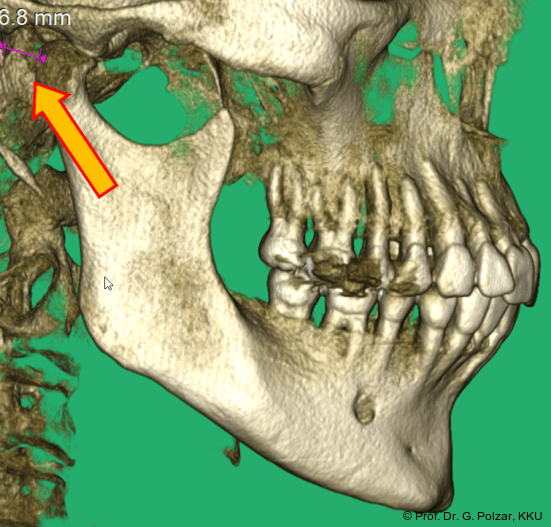

Im Sagittalschnitt zeigen beide Kiefergelenke eine deutlich anteriore Position. Der dorsokraniale Abstand betrug rechts 7,0 mm und links 5,8 mm. In der PEP waren sie im lateralen Bereich ca. 1 mm kleiner als in der Mitte der Sagittalprojektion (Abb. 6a–d).

Diese deutlich anteriore Gelenkposition im Neutralbiss ließ den Verdacht auf einen Sunday Bite zu. Das heißt, die Patientin schob den Unterkiefer aktiv nach vorne, um damit schönere Schneidezahnkontakte bzw. eine vermeintlich neutrale Okklusion zu erreichen. Nach mühsamen Lockerungsübungen gelang es der Patientin, auch in die zen­trale Kiefergelenkposition zu wechseln. So zeigte sich das ganze Ausmaß der Malokklusion. In neutraler KG-Position hatte die Patientin eine sagittale Frontzahnstufe von ca. 7 mm mit 1 PB Klasse II-Okklusion im Seitenzahn­bereich (Abb.5a+b, 7a–c).

Beide Kiefergelenke (KG) befinden sich nun in zentraler Kondylen-/Fossa-Position bei neu­traler Okklusion (Abb. 10+11).